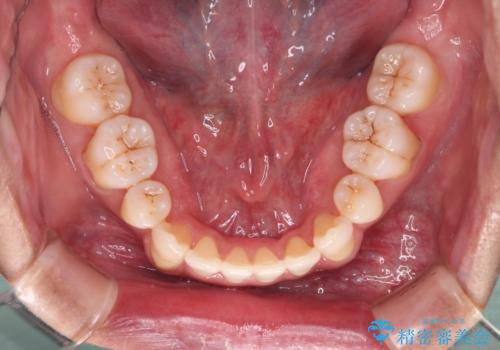

- 治療計画

叢生量が大きいため、上下顎両側4番を抜歯しました。矯正治療による歯肉退縮の著しい悪化もなく、主訴であるガタつきも改善できました。